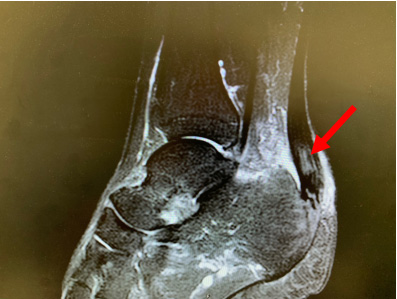

● 核磁共振可以表现为跟腱增厚增粗,局部信号改变。